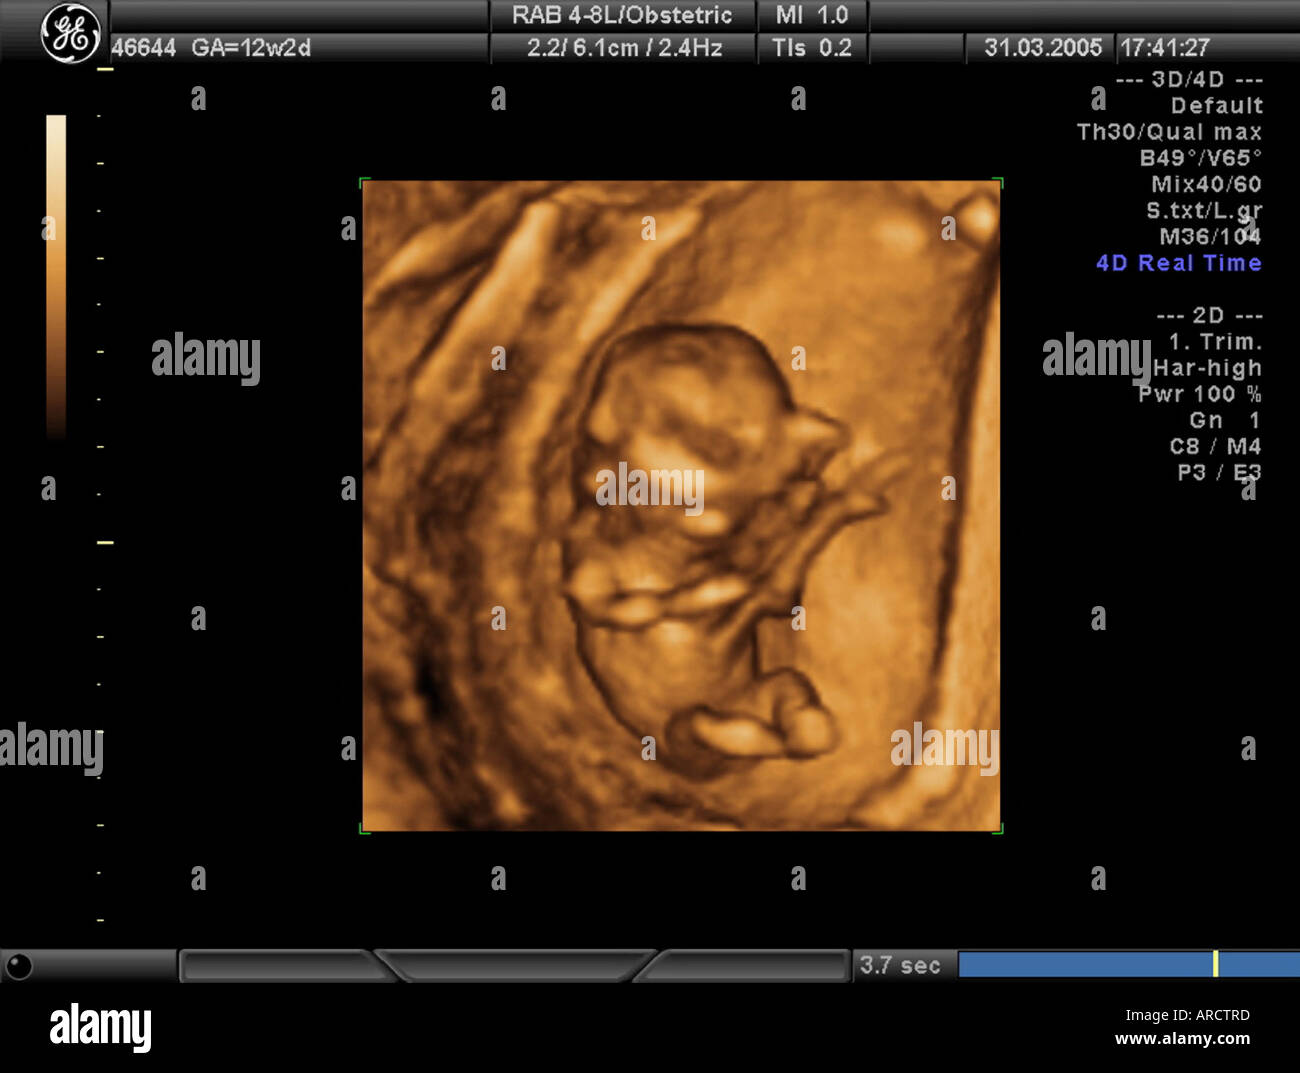

Source: erptalsoc.pages.dev Une échographie 3D d'un singleton fœtus à 12 semaines de grossesse Banque D'Images, Photo Stock , Echographie 3D : quand est-elle pratiquée ? Certains praticiens proposent de réaliser une écho 3D dès l'échographie du premier trimestre.Toutefois, pour obtenir une belle photo d'un bébé bien joufflu, Danièle Combourieu conseille d'attendre le 3ème trimestre de la grossesse et l'échographie des 7 mois et demi L'échographie de plaisir ne comporte aucun risque, ni pour le bébé ni pour la.

Source: irsusakpj.pages.dev 5th months pregnancy 4d ultrasound YouTube , Elle nous montre une image statique en trois dimensions du foetus et de ses structures avec des couleurs plus nettes que le noir et blanc de l'échographie traditionnelle. About Press Copyright Contact us Creators Advertise Developers Terms Privacy Policy & Safety How YouTube works Test new features NFL Sunday Ticket Press Copyright.

Babycocoon 3D Institut d'Échographie 3D prénatale à Gland Plus qu'une échographie 2D classique, l'échographie 3D permet de distinguer de manière plus précise les traits de son futur bébé Le temps d'exposition aux ultrasons ne dépasse pas 20 min, le mode "doppler" n'est pas utilisé et trois échographies au maximum sont réalisées par. C'est un moment où ils peuvent découvrir leur bébé en images, le voir grandir et se développer dans le ventre de la maman.